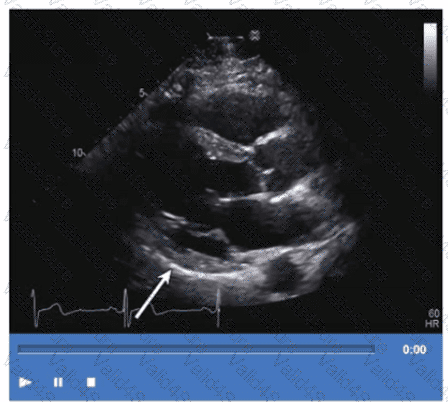

Which maneuver aids in uncovering potential diastolic dysfunction while performing pulsed wave Doppler of the mitral valve?